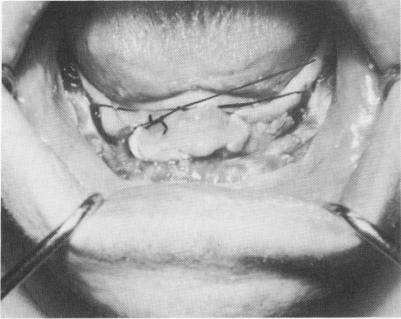

tissues should be sutured so that the tongue is kept in the posterior portion of the mouth and does not interfere with the impression. This is done by simply suturing the posterior aspect of the tissue on one side with the more anterior tissue on the opposite side of the arch, and vice versa (Fig. 12-12). The

Fig. 12-12. The lingual tissue was sutured from one side to the other in a criss-cross fashion to lock the tongue away from the exposed bone so that it would not interfere with the impression, and to keep the lingual tissue away from the bone for more access of the surgical tray, so that it would fit directly over the bone for the impression.